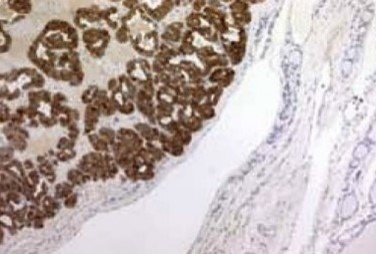

Figure 7 . Epithelial cells with an organoid and trabecular pattern with positive immunohystochemical staining for calcitonin .